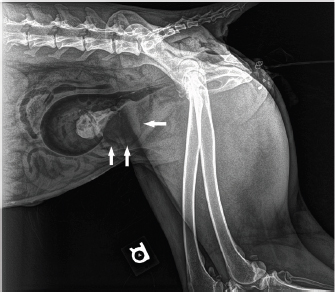

On examination, the wolf was moderately dehydrated. The urinary bladder was extremely firm, measuring 7.5 × 7.5 × 15cm3. In-house blood work was unremarkable. On ultrasound, the urinary bladder was filled with a homogenous mass of mixed echogenicity, with no evidence of a lumen. The bladder was catheterized with an 8 Fr polypropylene catheter and hemorrhagic urine with tissue clots flowed out. A double-contrast cystogram was performed by placing iohexol (1.3 ml/kg; Omnipaque 240 mgI/ml; GE Healthcare, Marlborough, MA) followed by air (5.3 ml/kg) into the bladder, outlining a mass at the caudoventral bladder wall (Fig. 1).

Fig. 1. Lateral radiograph of a double contrast cystogram in a maned wolf. Note the irregular mucosal and serosal outlines of the bladder caudoventrally (arrows). A mass involving the wall is highlighted.